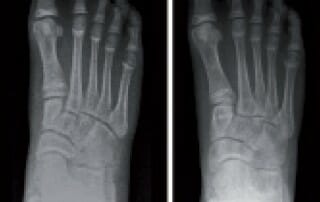

Gelenkerhaltende Korrektur der Planovalgus-Deformität

Diagnostik, Behandlungsoptionen sowie Grenzen einer Korrektur Operative Korrekturen von Planovalgusdeformitäten nach Wachstumsabschluss kommen bei vier Patientengruppen in Betracht: Jugendliche mit schweren flexiblen Deformitäten, bei denen eine Wachstumslenkung durch Arthrorise nicht [...]